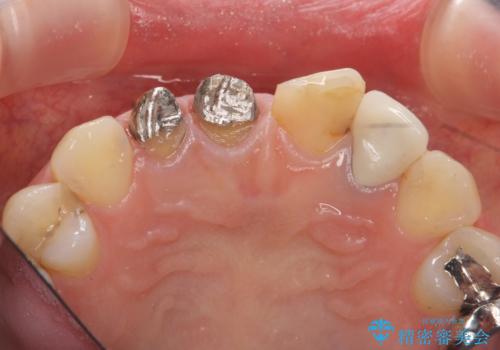

- 前歯を天然の歯のようにきれいにやりかえたいと希望され来院されました。

根尖病変の存在が判明したため、感染根管治療後にオールセラミックジルコニアクラウンを製作します。